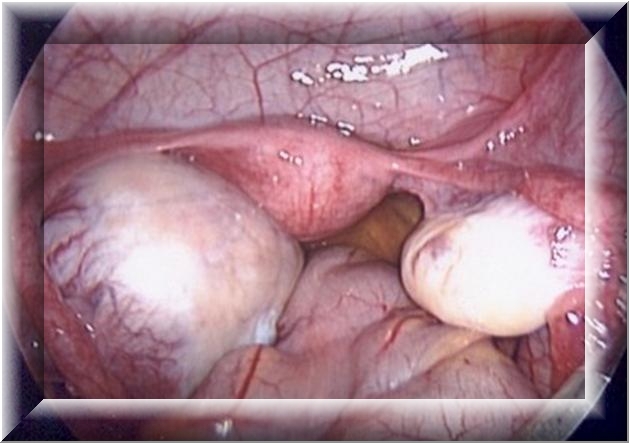

- Лапароскопии. Специальный оптический прибор вводится через брюшную стенку в полость живота для осмотра яичника и тридермомы. Зрелая опухоль на длинной тонкой ножке (бело-жёлтого цвета) чаще всего определяется между мочевым пузырём и маткой. Незрелая тератома обнаруживается сбоку от матки, имеет неоднородную консистенцию и неправильную форму.

При удалении тератомы яичника обнаруживаются зубы, волосы и другие образования